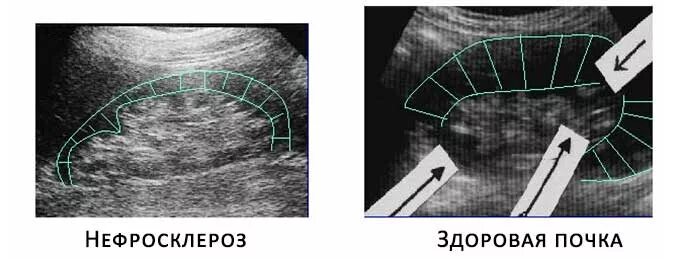

Нефросклероз почек на узи что это такое